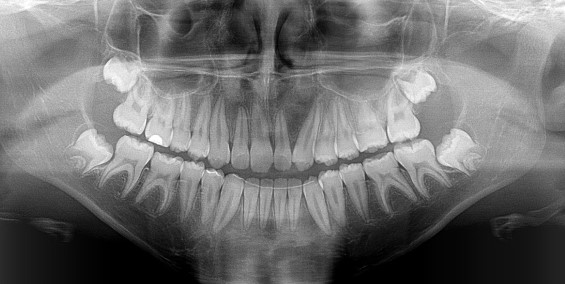

This is a vast field mostly involving surgery of some kind. Dr Coetzee does have a 3D Scanner in his practice to identify impacted teeth and will do the less complicated removal of impacted teeth that can be done under local anaesthetic in his rooms, but when general anaesthetic is required because of the severity of the impaction he will refer you to one of the maxillofacial specialist in his network, always placing you in the best hands for the treatment needed.